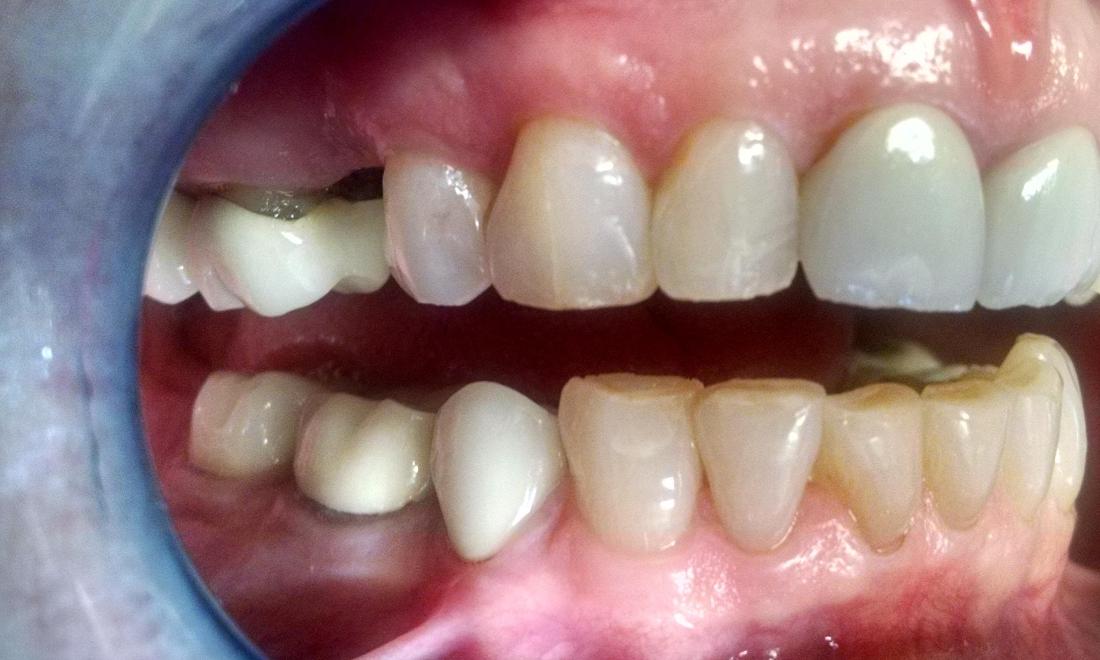

This wonderful patient came to us all the way from Colorado to have a dental implant done. At her first evaluation appointment, an x-ray was taken and Dr. Jordan determined that a minor sinus lift was needed to allow room for a dental implant. The sinus lift and insertion of the dental implant went perfectly! After healing, a tooth colored crown was placed on top of the implant and as you can see, it looks very life-like. She was very pleased.